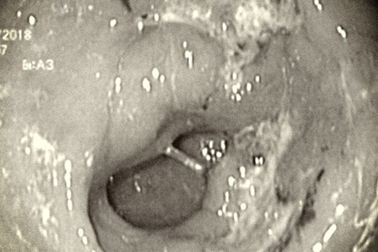

Ung thư đường tiêu hóa: Cơ hội nội soi can thiệp khi phát hiện sớmBệnh nhân ung thư luôn ám ảnh bởi các phương pháp điều trị, đặc biệt với phẫu thuật. Tuy nhiên nếu phát hiện ở giai đoạn sớm, bệnh nhân có thể tránh được cuộc mổ mở bằng can thiệp nội soi.

Phát hiện ung thư dạ dày nhờ dấu hiệu cảnh báo phổ biến2 năm nay, bà Thu (71 tuổi, Nam Định) thường xuyên bị đau bụng thượng vị. Gần đây, thấy cơn đau tăng dần, thậm chí nôn ra máu, đi ngoài phân đen, bà mới đi viện và được chẩn đoán bị ung thư dạ dày.

Loại ung thư phổ biến nhưng hàng nghìn ca chỉ phát hiện 30 ca giai đoạn sớmTại bệnh viện (BV) K Trung ương, mỗi năm có hàng nghìn trường hợp điều trị ung thư dạ dày nhưng chỉ có khoảng 30 ca là được phát hiện sớm. Căn nguyên là do người dân vẫn ngại việc tầm soát, khám định kỳ để phát hiện sớm ung thư. Trong khi đó, nếu phát hiện sớm, hiệu quả điều trị tốt hơn nhiều lần so với ung thư xâm lấn phải phẫu thuật.